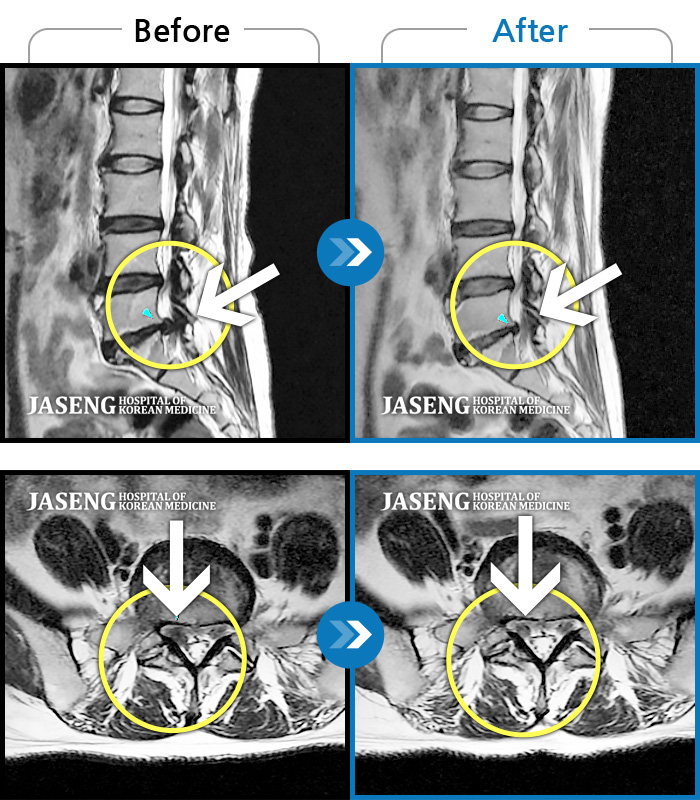

허리디스크

보라매 · 왕오호 원장

좌측 허리 통증 및 좌측 다리 저림

촬영시기

2016.05.21 ~ 2018.04.13

2018.12.28